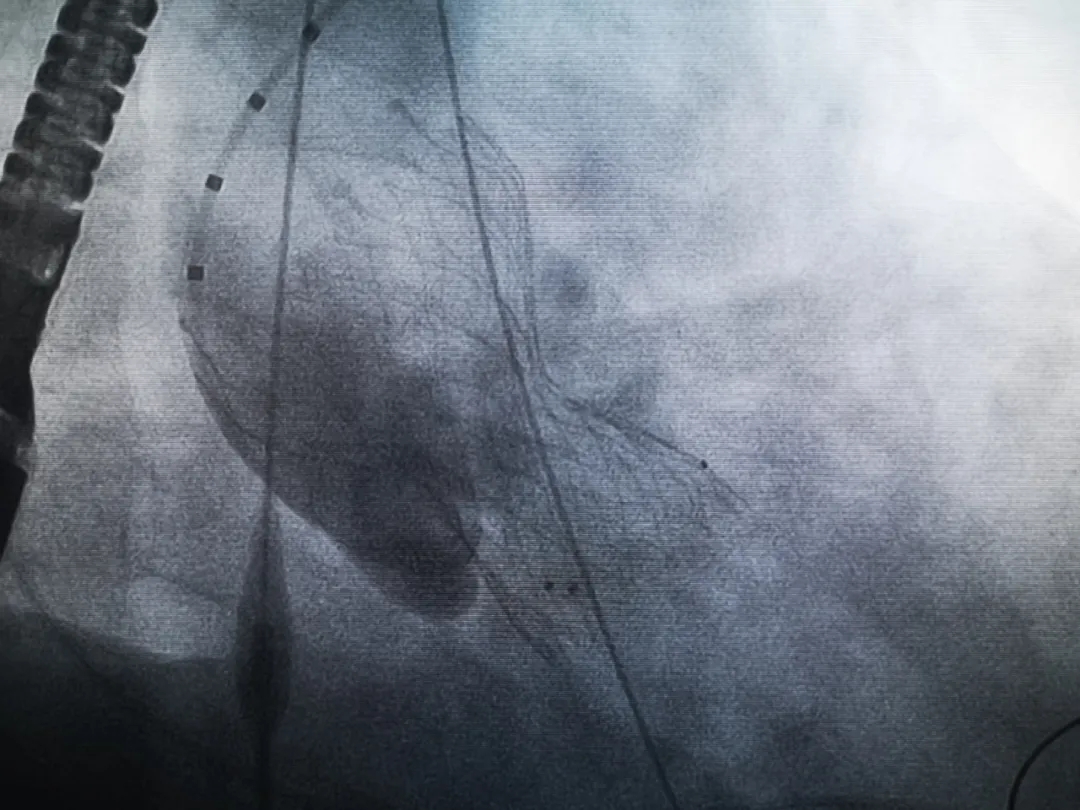

手術(shù)過程緊張而有序,心臟沒有停跳,也沒有太大的血壓波動;球囊擴(kuò)張的恰到好處,瓣膜釋放之后超聲醫(yī)生的評估是至關(guān)重要的,因?yàn)槲覀兲崆熬蜏?zhǔn)備了后擴(kuò)張,也準(zhǔn)備了瓣中瓣,甚至還準(zhǔn)備了瓣周漏封堵。所幸的是,超聲診療中心劉夢梅醫(yī)生說:沒有返流、沒有瓣周漏,瓣膜形態(tài)良好,跨瓣壓差約17mmHg(相較于術(shù)前的87mmHg還是可以接受的)。瓣膜置入的成功并不是慶祝的時候,從戰(zhàn)場撤退仍然需要謹(jǐn)慎。由于王子特別胖,腹股溝區(qū)脂肪尤為肥厚,在股動脈插管拔除、確認(rèn)搏動正常之后,便逐層縫合。同時為了美觀、縫合之后不至于鼓個包出來,我們又仔細(xì)剪除了部分脂肪。術(shù)后次日,王子便可以下床活動了。